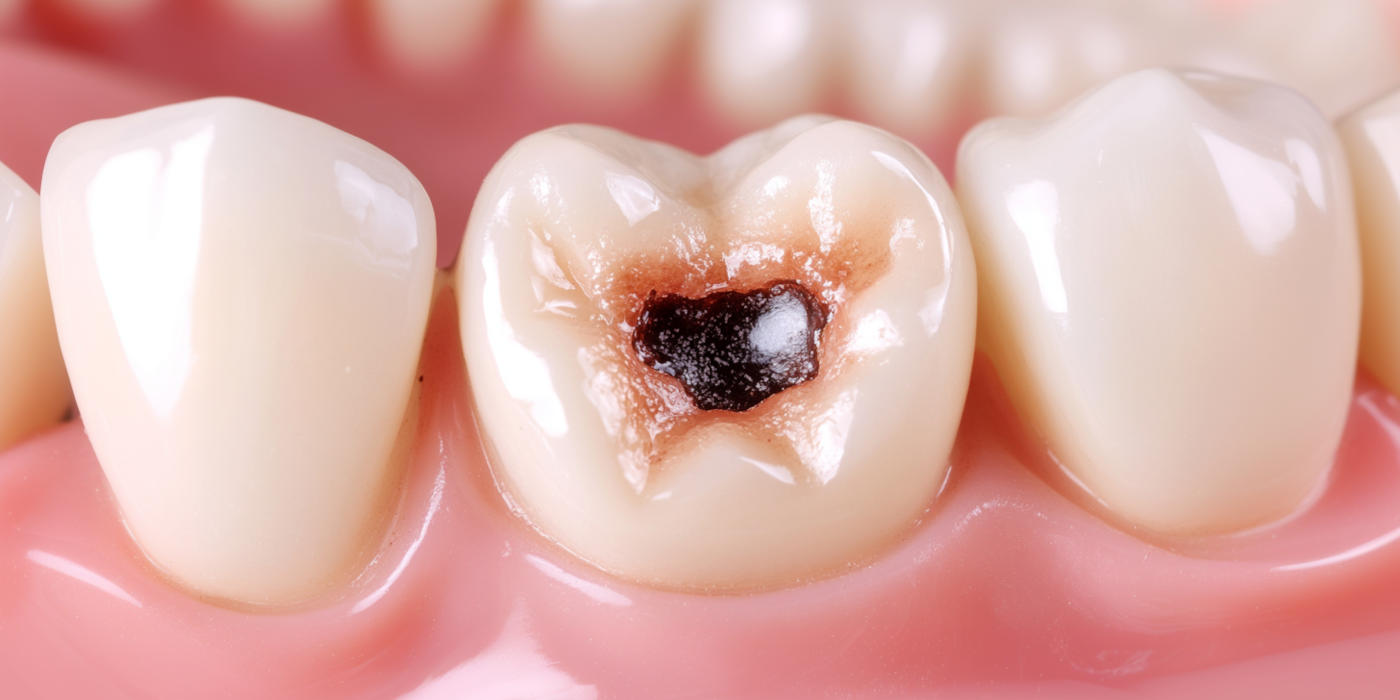

Implants dentaires Blanchiment dentaire Apnée du sommeil Facettes dentaires Les caries Traitement endodontique Prothèses dentaires Soin des gencives - Parodontie Dents de sagesse Urgence dentaire Hygiène bucco-dentaire Vidéos pédagogiques Vos dents à tout âge